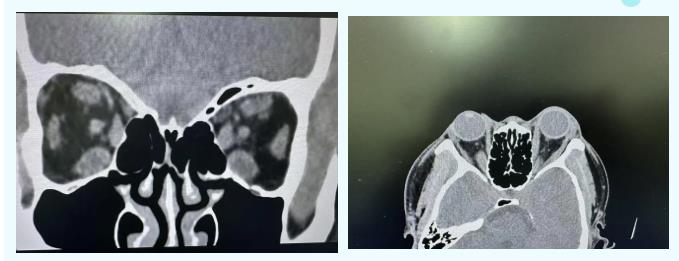

此次接受手术的患者,便是被甲状腺相关眼病困扰多年的典型病例。该患者患病以来眼球突出症状逐年加剧,同时伴随持续性眼睑退缩、眼部胀痛、畏光流泪、视物模糊不清等问题,辗转省内多家医院治疗,效果始终不尽如人意,病情逐渐恶化,正常的工作、生活完全被打乱。抱着最后一线希望,患者慕名前往青海红十字医院眼科就诊。科室主任接诊后高度重视,第一时间联动薛尚才教授团队,为患者开展全方位、精细化的眼部及全身检查,精准把控病情发展程度、眼眶解剖结构等关键信息。

针对患者复杂的病情,医院迅速牵头组建多学科诊疗团队,联合内分泌科、麻醉科等相关科室专家开展多次联合会诊。专家团队全面评估手术风险、细致排查手术禁忌,针对眼眶解剖结构复杂、手术操作空间狭小、需精准避开血管神经等诸多难点,反复研讨、优化手术方案,最终确定实施眶减压术这一针对重症患者的最优治疗方案,为手术成功实施筑牢根基。

眶减压术是治疗重症甲状腺相关眼病的高精尖手术,对手术团队的解剖知识、操作精度、临床经验要求极为严苛。手术核心在于通过微创方式去除眼眶部分骨壁、减除多余眶内脂肪,在不损伤眼部关键组织的前提下,科学扩大眼眶容积,快速降低眶内高压,从根源上缓解眼球突出,解除视神经压迫,实现保护视力、改善眼部外观的双重治疗目标。手术过程中,薛尚才教授团队全程专业指导、精准把控,青海红十字医院眼科团队凭借扎实的理论基础、娴熟的显微操作技巧,在高倍显微镜下细致分离眼眶组织,小心翼翼避开各类血管、神经等重要结构,每一步操作都精准无误,全程手术平稳有序,无任何并发症发生,圆满完成手术操作。